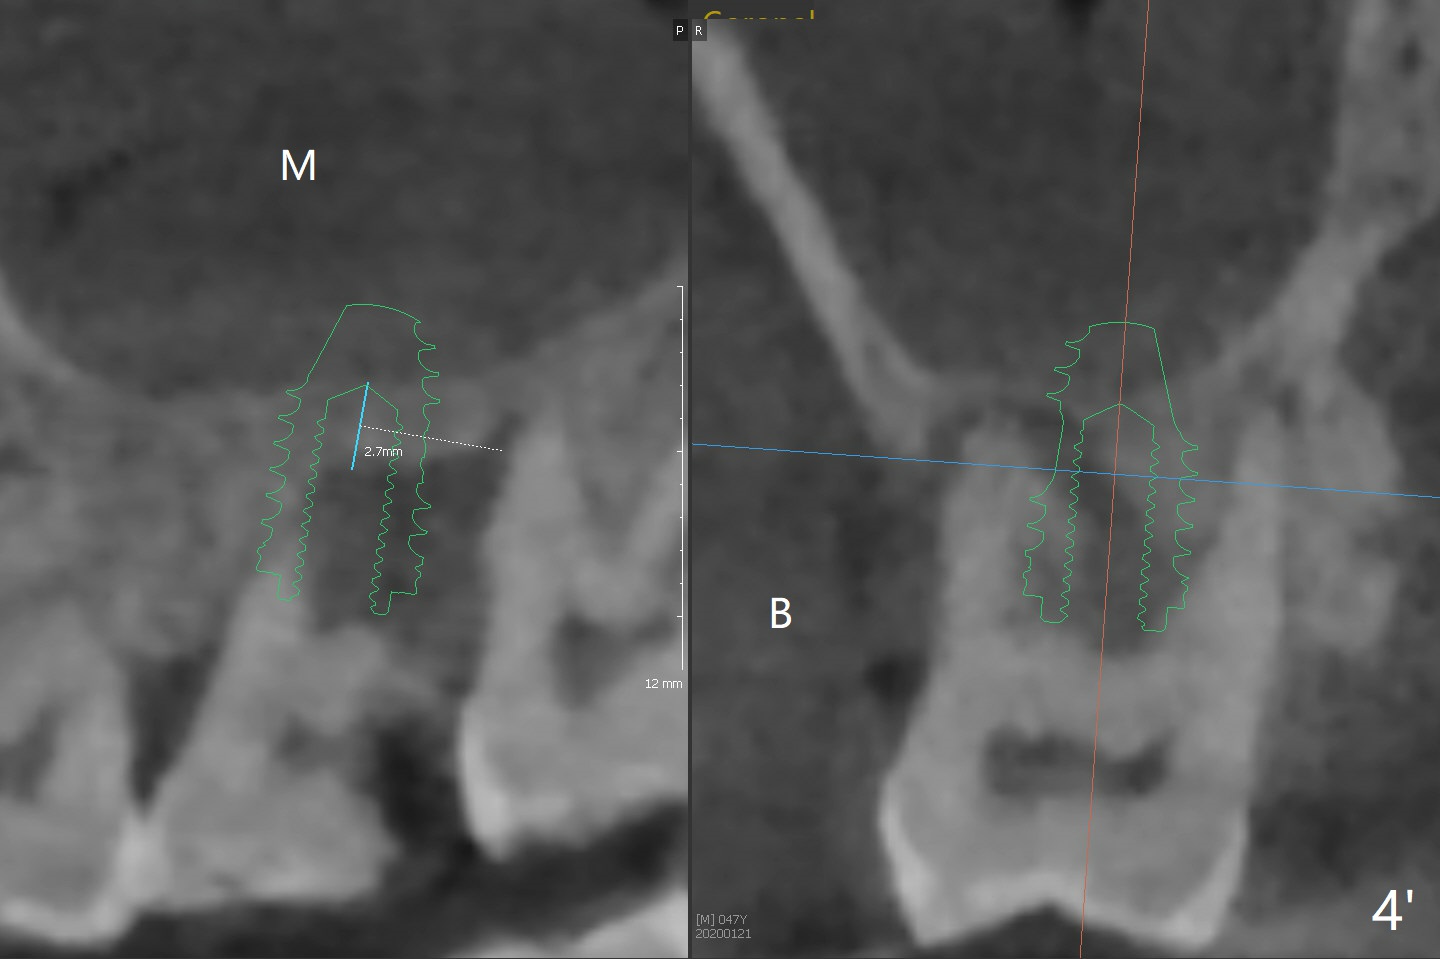

Note the bone height (2.7 mm) at #2 and the thick sinus membrane (M, Fig.2' (easy for sinus lift)) .  B: buccal.  The thick membrane or IBS implant is not requisite for success.